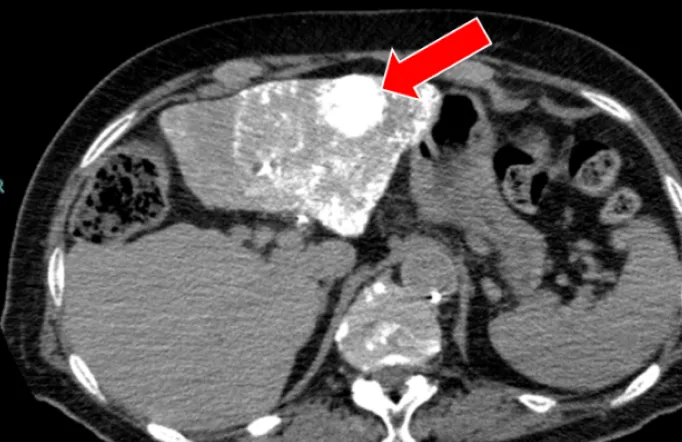

肝がんの検査には、血液検査と超音波(エコー)検査(写真2)、CT検査(写真3)、MRI検査といった画像検査を組み合わせて行います。CT検査やMRI検査では造影剤を使用して詳細な検査を行いますが、腎機能低下や透析症例でも安全に使用できる「造影剤」を用いて行う造影エコー検査(写真4)も週1回外来で行っています。

• (写真3)肝がんの造影CT写真